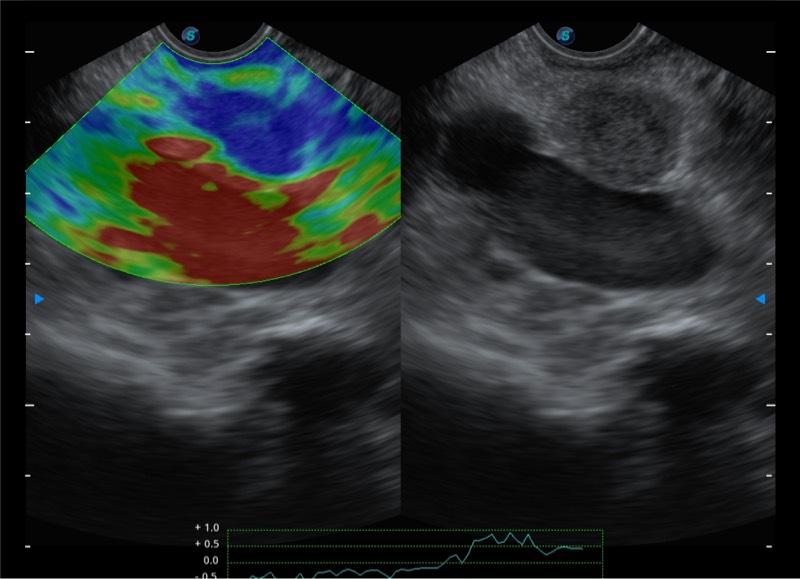

搭载百万级CMOS成像技术

及自主研发凸阵换能器,

可呈现优质的内镜和超声画面

基于二十年的超声技术积累,乐玩lewin国际提供了最新一代的独立超声主机,在提供高质量图像的同时满足多学科使用。具备常见多普勒技术并提供弹性成像、声学造影等高端影像技术。新一代传感器具有更强的抗干扰能力并减少图像伪影。